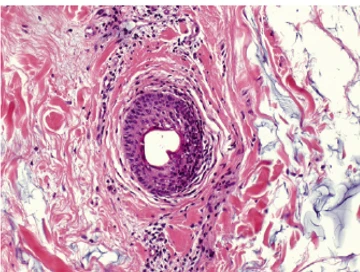

Дальнейшие результаты оценивались на 14-й и 30-й день после инъекции (рис. 1, 2).

Рис. 1. Окрашивание гематоксилин-эозином, x 20, E - эпидермис, LY - лимфоциты, PZ - плазмоциты, EG - эозинофильные гранулоциты, FM – инородный материал.

Surgiderm® 24XP. Выраженное хроническое воспаление, инфильтрация лимфоцитами и плазмоцитами LY, PZ.

Belotero® Basic. Гистоморфологическая реакция воспаления отсутствует.

Результаты эксперимента показали отсутствие признаков воспалительной реакции в ответ на введение только двух филлеров на основе ГК – Belotero® Balance и Belotero® Intense (рис. 1, 2), в то время как все другие филлеры показали признаки хронической воспалительной реакции. Значительного различия между результатами исследования образцов, взятых через 14 и 30 дней после введения, отмечено не было.